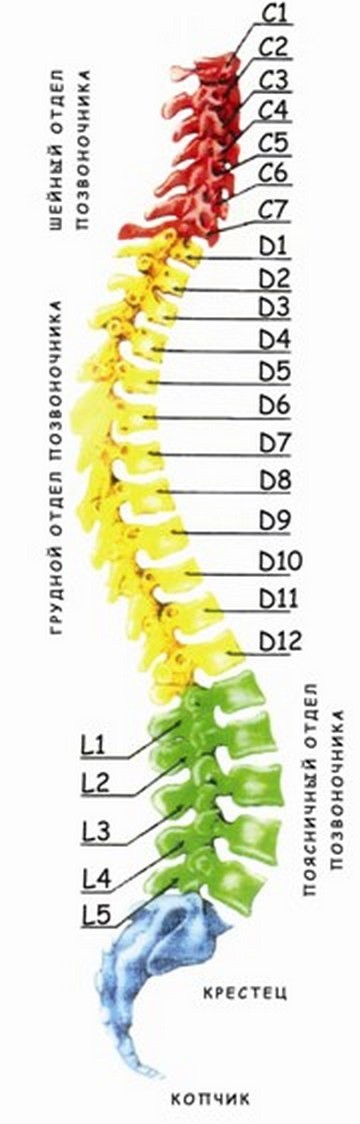

Позвонок Th10: анатомия и фото медицинских иллюстраций